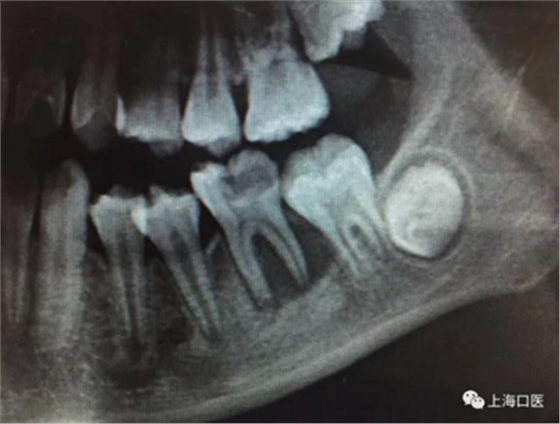

這是上海武廣增正畸工作室接診的一例非常規(guī)拔牙矯治病例,患者女性,初診年齡14歲。LL6殘冠拔除。LL7近中平移取代LL6,我們上傳了該患者一組下頜磨牙近中平移連續(xù)矯治過程的正畸X線片,與正畸界朋友分享。